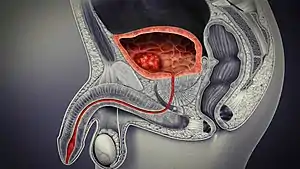

In males, the prostate gland lies outside the opening for the urethra. The middle lobe of the prostate causes an elevation in the mucous membrane behind the internal urethral orifice called the uvula of urinary bladder. The uvula can enlarge when the prostate becomes enlarged.

The bladder is located below the peritoneal cavity near the pelvic floor and behind the pubic symphysis. In males, it lies in front of the rectum, separated by the recto-vesical pouch, and is supported by fibres of the levator ani and of the prostate gland. In females, it lies in front of the uterus, separated by the vesico-uterine pouch, and is supported by the elevator ani and the upper part of the vagina.[8]

The human bladder derives from the urogenital sinus, and it is initially continuous with the allantois. The upper and lower parts of the bladder develop separately and join around the middle part of development.[5] At this time the ureters move from the mesonephric ducts to the trigone.[5] In males, the base of the bladder lies between the rectum and the pubic symphysis. It is superior to the prostate, and separated from the rectum by the recto-vesical pouch. In females, the bladder sits inferior to the uterus and anterior to the vagina; thus its maximum capacity is lower than in males. It is separated from the uterus by the vesico-uterine pouch. In infants and young children the urinary bladder is in the abdomen even when empty.[16]